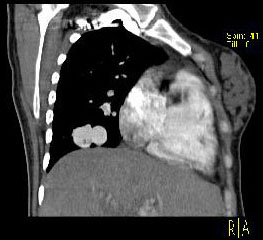

男性,26岁,头晕、气逼三年余,CT检查如图所示,请选择的最可能诊断 ( ) XN-27051.jpg XN-27052.jpg XN-27053.jpg XN-27054.jpg

题型: 单选题 分类: 心血管内科

• D.动静脉畸形